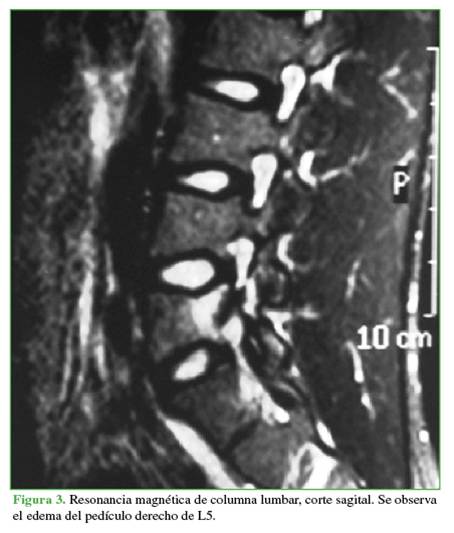

Se tomaron radiografías de columna lumbar, de frente, de perfil y oblicuas que revelaron esclerosis del pedículo derecho y espondilólisis izquierda de L5. La tomografía computarizada mostró, además de la lesión antes descrita, una solución de continuidad en el pedículo derecho, con márgenes escleróticos e hipertróficos (Figuras 1 y 2). En la resonancia magnética, se visualizó un edema en dicho pedículo lumbar (Figuras 3 y 4).

Un rasgo habitual en la pediculólisis es la esclerosis del pedículo, pero aún no resulta claro si esto representa un fenómeno de adaptación anterior a la fractura o si es una consecuencia de ella.9 Esta esclerosis unilateral le da el aspecto de vértebra anisocórica en la imagen radiológica. Sin dudas, la tomografía computarizada permite evaluar mejor el cuadro, realizar diagnósticos diferenciales, controlar la evolución y, en algunos casos, efectuar una planificación terapéutica. Las características suelen ser la presencia de solución de continuidad radiolúcida con márgenes escleróticos e hipertróficos.4 La resonancia magnética tiene una elevada sensibilidad a la hora de diagnosticar este tipo de lesiones que, si bien puede mostrar o no el trazo de fractura a nivel del pedículo, sí manifiesta el edema

como una imagen hipointensa en la secuencia T1 e hiperintensa en la secuencia T2.3,4